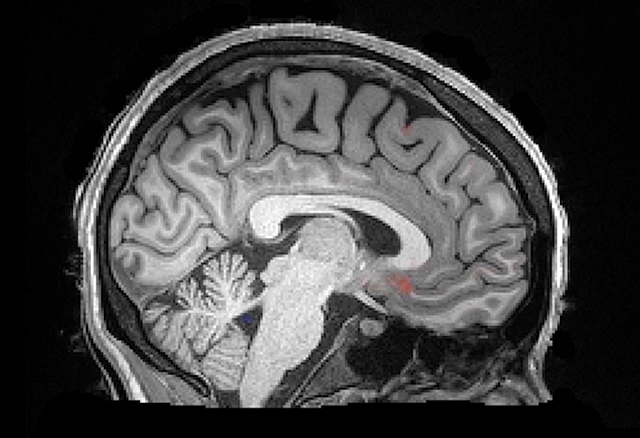

• Raymond Damadian: Resonancia Magnética

Raymond Damadian: Resonancia Magnética

En 1971 el doctor Raymond Damadian demostró que la resonancia magnética podía ser usada para detectar enfermedades porque distintos tipos de tejidos emiten señales que varían en su duración, en respuesta al campo magnético. Damadian creó la primer equipo de resonancia magnética en 1972. Permitiendo de esta manera ampliar el estudio del cerebro permitiendo ver afecciones cerebrales y detectar enfermedades.